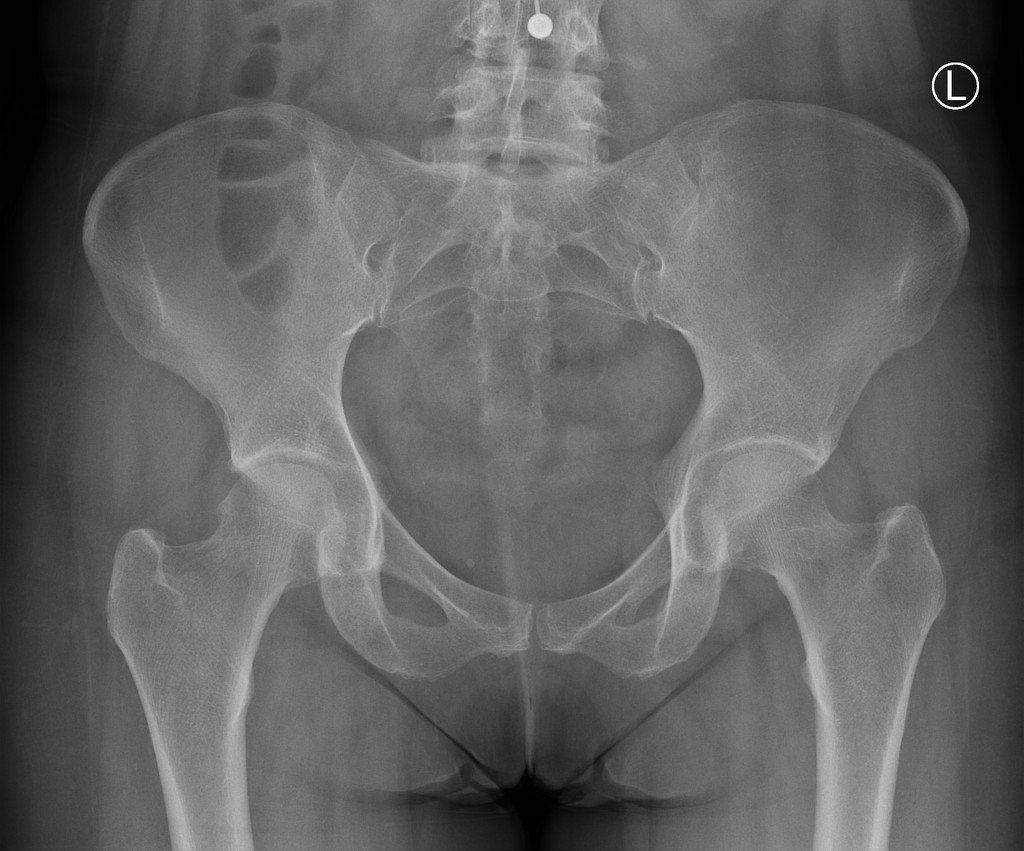

The greater trochanter is a bony prominence of the upper thigh bone which can be felt on the lateral aspect of the hip. It is the attachment site for a number of muscles that originate from the pelvis, namely the gluteal muscles. It is thought to affect 1.8 per 1000 patients annually.